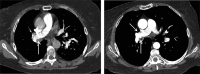

This is a case of a woman with massive hemoptysis, associated with a pulmonary artery pseudoaneurysm, and a fistula between the right pulmonary artery and bronchus intermedius. Bronchoscopic evaluation revealed an endobronchial mass in the right bronchus intermedius, suspicious for a tumor. Upon biopsy of the mass, massive bleeding occurred. The right lung was surgically resected. No specific etiology for the fistula was identified on pathologic examination. To our knowledge, this is the first report of a pulmonary artery-bronchial fistula presenting without typically known predisposing factors.